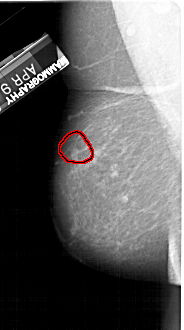

A_1435_1.LEFT_CC

LEFT_CC LINES 5311 PIXELS_PER_LINE 2746 BITS_PER_PIXEL 12 RESOLUTION 43.5 OVERLAY

FILE: A_1435_1.LEFT_CC.OVERLAY

TOTAL_ABNORMALITIES 1

ABNORMALITY 1

LESION_TYPE MASS SHAPE OVAL MARGINS ILL_DEFINED

ASSESSMENT 4

SUBTLETY 3

PATHOLOGY BENIGN

TOTAL_OUTLINES 1

BOUNDARY